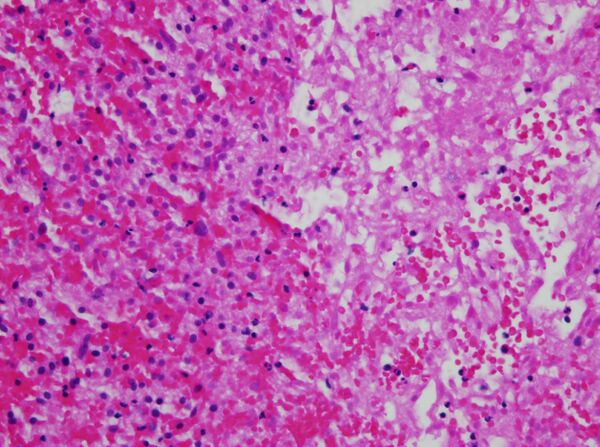

- Колликвационный некроз (или разжижающий некроз), в отличие от коагуляционного некроза, характеризуется разложением мёртвых клеток с образованием вязкой жидкой массы.[6] Это типично для бактериальных, а иногда и грибковых инфекций из-за их способности стимулировать воспалительную реакцию. Некротическая жидкая масса часто кремово-желтого цвета из-за присутствия мёртвых лейкоцитов и обычно известна как гной.[6] Гипоксические инфаркты в головном мозге представляют собой этот тип некроза, потому что мозг содержит мало соединительной ткани, но большое количество пищеварительных ферментов и липидов, и поэтому клетки могут быть легко перевариваемы их собственными ферментами.[5]

- Гиперэозинофилия цитоплазмы на образцах с гематоксилином и эозином.[16] Он виден как более темное пятно цитоплазмы.